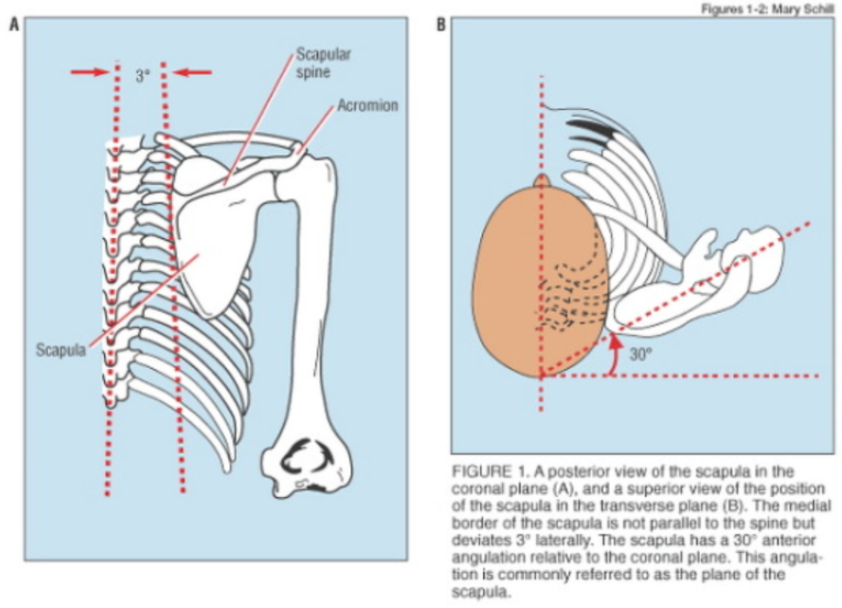

견갑골의 각도는 몸의 중심선(Coronal plane=frontal plane)으로부터 30 ~ 35도 기울어져 있고, 늑골에 거의 바짝 붙어있는것이 정상입니다.

일반적으로 팔을 벌리는(팔벌려 뛰기 동작) 외전과 다르게 견갑골 관절면(Scapular plane)을 따라서 팔을 들어올리는 것을 스캡션(Scaption) 이라고 하는데요.